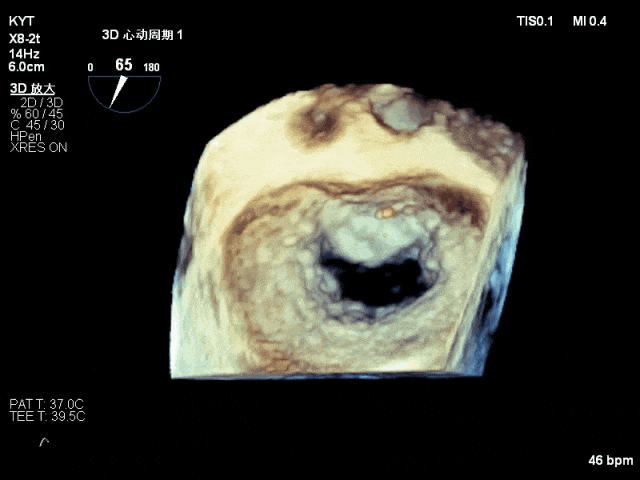

放置第一枚NTR夹合器后的TEE 3D影像,瓣叶脱垂明显改善